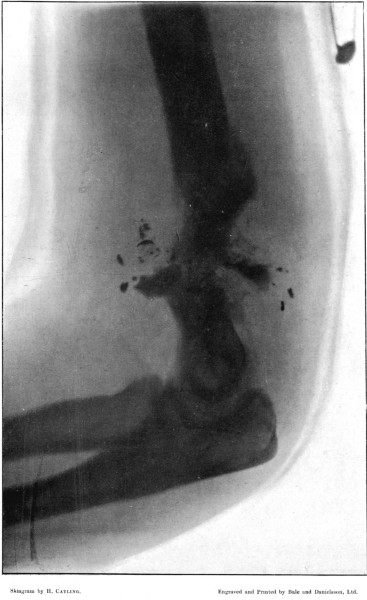

3. Punctured Fracture of Clavicle162

4. Comminuted Fracture of Shaft of Humerus180

5. Comminuted Fracture of Humerus accompanied by an Explosive Exit182

6. Comminuted Fracture of Humerus due to Oblique Impact184

7. Same Fracture healed186

8. Low Velocity Fracture of Humerus With Retained Bullet188

9. Localised Fracture of Humerus Showing Fragmentation of the Bullet190

10. Wedge-shaped Fracture of the Radius192

11. Fracture of the Metacarpus, showing Fragmentation of the Bullet194

12. Finely Comminuted Fracture of the Femur196

I am greatly indebted to my former colleague Mr. Cheatle for two of the illustrations of wounds, and for permission to quote some of his other experience, and to Mr. Henry Catling, to whose skill I owe the majority of the skiagrams of the fractures under my observation at Wynberg and elsewhere.